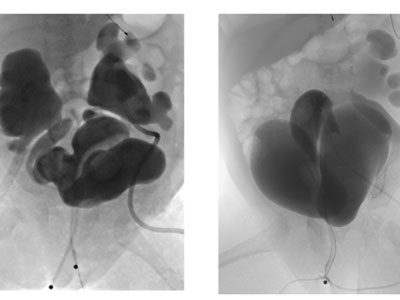

Childhood Polycystic Kidney Disease

The Hepatorenal Fibrocystic Disease (HFRD) Translational Core Center was founded in 2005 by Lisa Guay-Woodford, MD, during her tenure at the University of Alabama at Birmingham and funded through an National Institutes of Health P30 mechanism. Autosomal recessive polycystic kidney disease (ARPKD) and other hepatorenal fibrocystic diseases are relatively rare recessive disorders, but constitute an important set of childhood nephropathies.